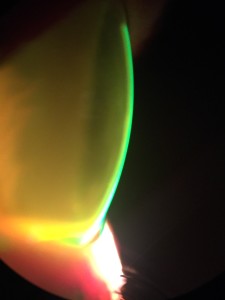

Esta semana quiero comentar este estudio cuyo propósito fué investigar las tasas de éxito y fracaso de la adaptación de la lente escleral en el queratocono grave. Para ello se diseño un estudio de series de casos retrospectivos.

Se propuso la adaptación de lentes esclerales para los 75 ojos incluidos en el estudio. Ocho ojos se sometieron a una cirugía de trasplante debido a la agudeza visual insuficiente con las lentes, intolerancia a los lentes y problemas con el manejo de los lentes. Doce ojos no fueron adaptados debido a la buena agudeza visual en el otro ojo o una contraindicación para el uso de lentes. Tres ojos se adaptaron con éxito con lentes corneales o híbridas. Se prescribieron lentes esclerales en 51 de 75 ojos. La ganancia media en la agudeza visual (lente versus agudeza visual corregida con gafas) fue de 0.54 ± 0.18 (fracción decimal, optotipo Snellen). Siete ojos se perdieron durante el seguimiento, cuatro ojos abandonaron el uso de la lente escleral debido a la incapacidad para manejar las lentes, y cuarenta ojos usaron las lentes en su última visita de seguimiento, con un intervalo de seguimiento promedio de 30.15 ± 12.83 meses.

En conclusión, cuarenta de los 51 ojos con queratocono grave que de otra forma se habrían sometido a cirugía de trasplante se trataron con éxito con el uso de lentes esclerales a largo plazo. De esta manera, la indicación de queratoplastia se redujo a menos de la mitad en esta población de queratocono. Hoy en día, y siempre que no haya una evolución del Queratocono, la lente escleral es una excelente opción de tratamiento.